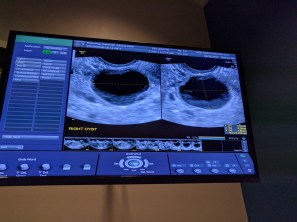

We have met with our OB once already 2 weeks ago and have another appointment on Tuesday. Because we are having twins the pregnancy is considered high risk so our OB wants to do extra monitoring with us. We will be getting an ultrasound done every 4 weeks starting on Tuesday to track the twins’s growth and make sure they are on track. His biggest concerns right now are preeclampsia, gestational diabetes, and that one twin doesn’t grow as much as the other. He said that some differences in size is normal since they are siblings but he doesn’t really want to see more than 20% difference in size. Preeclampsia and gestational diabetes are both more common in twin moms because they are caused by hormones and having 2 placentas increases that.

My cycle has finally started back up again so we had a baseline ultrasound with Dr. Amols. My uterus looked great, but while he was checking the measurements for it Dr. Amols noticed a problem.